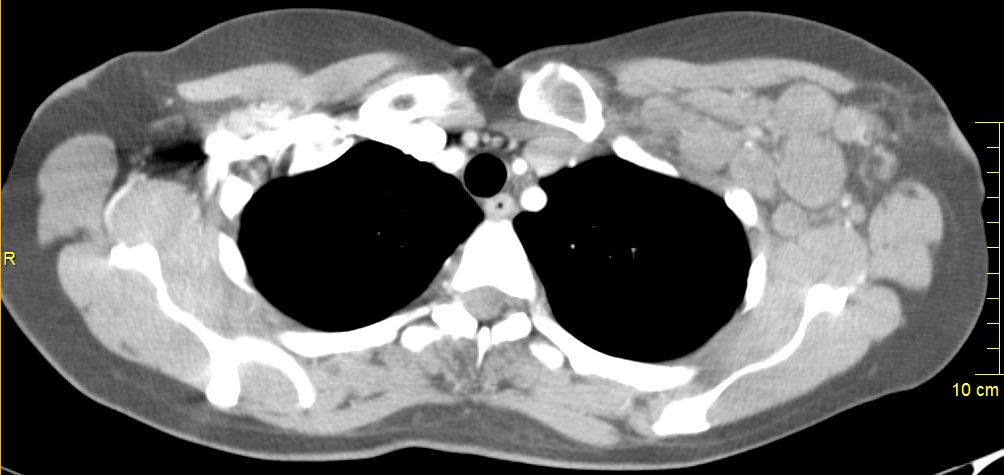

52-jährige Frau, bei der vor einem Jahr ein 15 mm großes invasiv-duktales Mammakarzinom rechts o/iq nach 3 Wochen Letrezol (Adapt-Studie) operiert wurde.

Postoperativ ypT1c, ypN0 (0/2 sn), cM0, L1 V0 R0, G2, ER: 6/12, PR: 0/12, HER-2/neu: negativ, Ki-67: 30%, Oncotype DX Recurrence Score 40.

CHT: 8 x nabPaclitaxel -> 4 x EC.

Dann Bestrahlung der Brust.

AHT mit Letrozol.

Jetzt palpable Lymphknotenmetastasen supraklavikulär rechts.

CT: Die teilweise rechts retroklavikulär hinter der rechten medialen Klavikula und supraklavikulär gelegenen Lymphknotenmetastase hat eine Größe von maximal 2,5 cm.

Weiter oberhalb und dorsalseitig sind im rechten unteren Halsdreieck dorsal der rechten Vena jugularis externa konfluierende inhomogene Lymphknoten mit Einzelgrößen bis zu 1,5 cm und einer Gesamtpaketausdehnung bis zu 4 cm sichtbar.